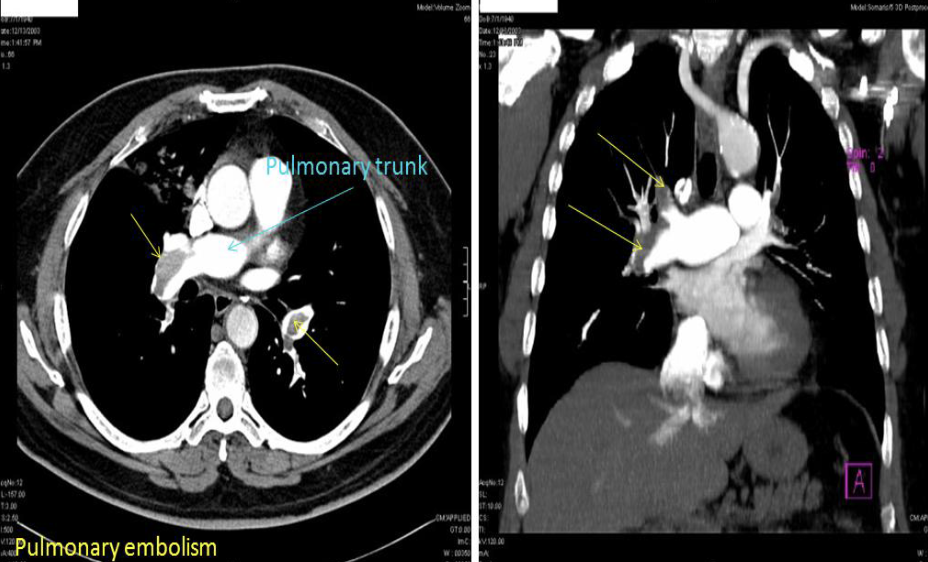

Axial and coronal CT chest with contrast. Thrombus in the pulmonary artery